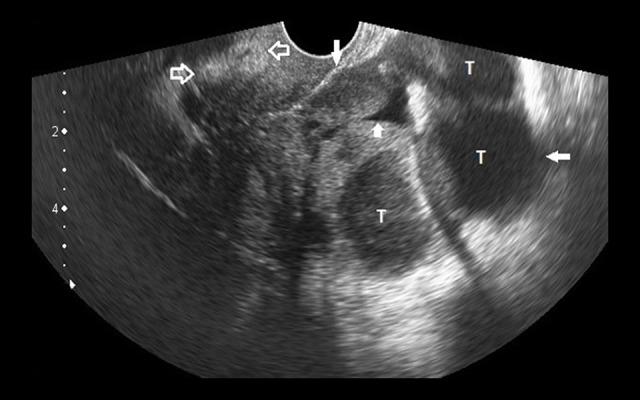

In this manuscript, we describe four cases of OHVIRA syndrome. Case 1 was a 34-year-old nulligravida, married since fourteen years, who presented with a 5-month history of pelvic inflammatory disease and dyspareunia. Regular menses in the patient and azoospermia in her husband delayed the diagnosis. Case 2 was a 14-year-old girl who presented with dysmenorrhea and lower abdominal pain since a few months. Case 3 was a 27-year-old female who presented with infertility and dysmenorrhea. Case 4 was a 15-year-old female who presented with a one-year history of dysmenorrhea and cyclic pelvic pain. In all cases, one of the uterine horns revealed collection due to a hemivaginal septum and an absent ipsilateral kidney; thus, establishing the diagnosis of OHVIRA syndrome. The case 4 additionally revealed homolateral vaginal agenesis.

在本手稿中,我们描述了4例OHVIRA综合征病例。病例1为一名34岁未孕女性,结婚14年,有5个月盆腔炎和性交困难病史。患者月经规律,丈夫无精子症,这延迟了诊断。病例2为一名14岁女孩,几个月来一直有痛经和下腹痛。病例3为一名27岁女性,有不孕和痛经症状。病例4为一名15岁女性,有1年痛经和周期性盆腔疼痛病史。在所有病例中,一个子宫角因半阴道隔和同侧肾脏缺如而出现积液,从而确诊为OHVIRA综合征。病例4还显示同侧阴道发育不全。